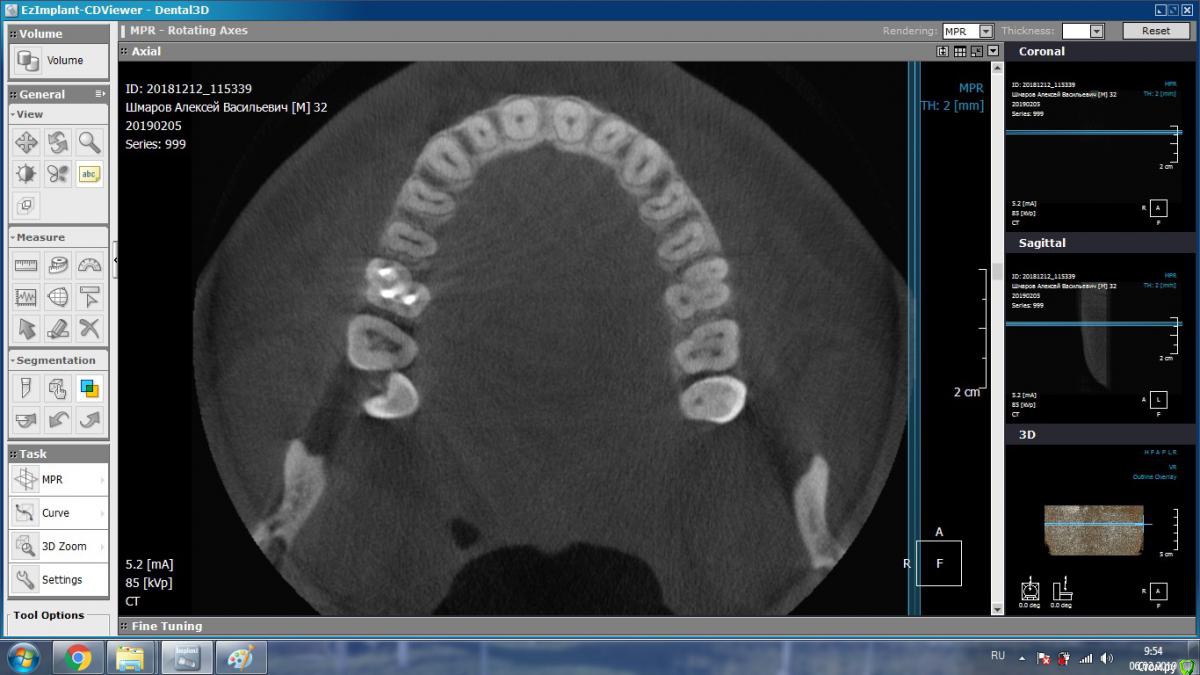

aleks.k Опубликовано 5 февраля, 2019 Автор Поделиться Опубликовано 5 февраля, 2019 Добрый день! Сделал КТ. Посмотрите пожалуйста.Есть 2 мнения очных стоматологов, пока никто из них КТ не видел, мнение на основании предыдущего панорамного снимка:1. Надо удалять 6 зуб справа2. Который и депульпировал 6 зуб сказал, что проблемы в 6 зубе нет, зуб мудрости нужно оттянуть брекетами. Размер файла 131 мб. http://fayloobmennik.cloud/7349278 Ссылка на комментарий

aleks.k Опубликовано 5 февраля, 2019 Автор Поделиться Опубликовано 5 февраля, 2019 Такие подойдут? Ссылка на комментарий

kramer Опубликовано 5 февраля, 2019 Поделиться Опубликовано 5 февраля, 2019 Судя по срезам, вероятнее причина в пульпите 7 зуба, возникшего в результате давления на него 8-ки. Ссылка на комментарий

DmitrySH Опубликовано 5 февраля, 2019 Поделиться Опубликовано 5 февраля, 2019 Такие подойдут? В Аксиальной проекции покажите еще несколько срезов Ссылка на комментарий

aleks.k Опубликовано 6 февраля, 2019 Автор Поделиться Опубликовано 6 февраля, 2019 Срезы Ссылка на комментарий

aleks.k Опубликовано 6 февраля, 2019 Автор Поделиться Опубликовано 6 февраля, 2019 Еще один срез, может быть более удачный чем первые в этой проекции Ссылка на комментарий

DmitrySH Опубликовано 6 февраля, 2019 Поделиться Опубликовано 6 февраля, 2019 Срезы Очень хорошо. Теперь как первые три, но увеличить 16 зуб. Остальные нам мало интересны, пазуха тоже Ссылка на комментарий

DmitrySH Опубликовано 7 февраля, 2019 Поделиться Опубликовано 7 февраля, 2019 В шестом зубе похоже еще 1 канал есть Ссылка на комментарий

DmitrySH Опубликовано 7 февраля, 2019 Поделиться Опубликовано 7 февраля, 2019 Я так понимаю что меня записали на удаление, по причине того, что стоматолог не обладает квалификацией для такого лечения? Ведь нужен именно эндодантист. Допустим что канал есть. Если его лечить, по цене примерно сколько это стоит? В Калуге думаю нет таких специалистов. Хотя бы примерно. И в случае лечения есть ли гарантия на такой зуб? Еще нужен микроскоп. Потому как если бы канал был хорошо виден, то его бы сразу нашли и обработали. Ссылка на комментарий